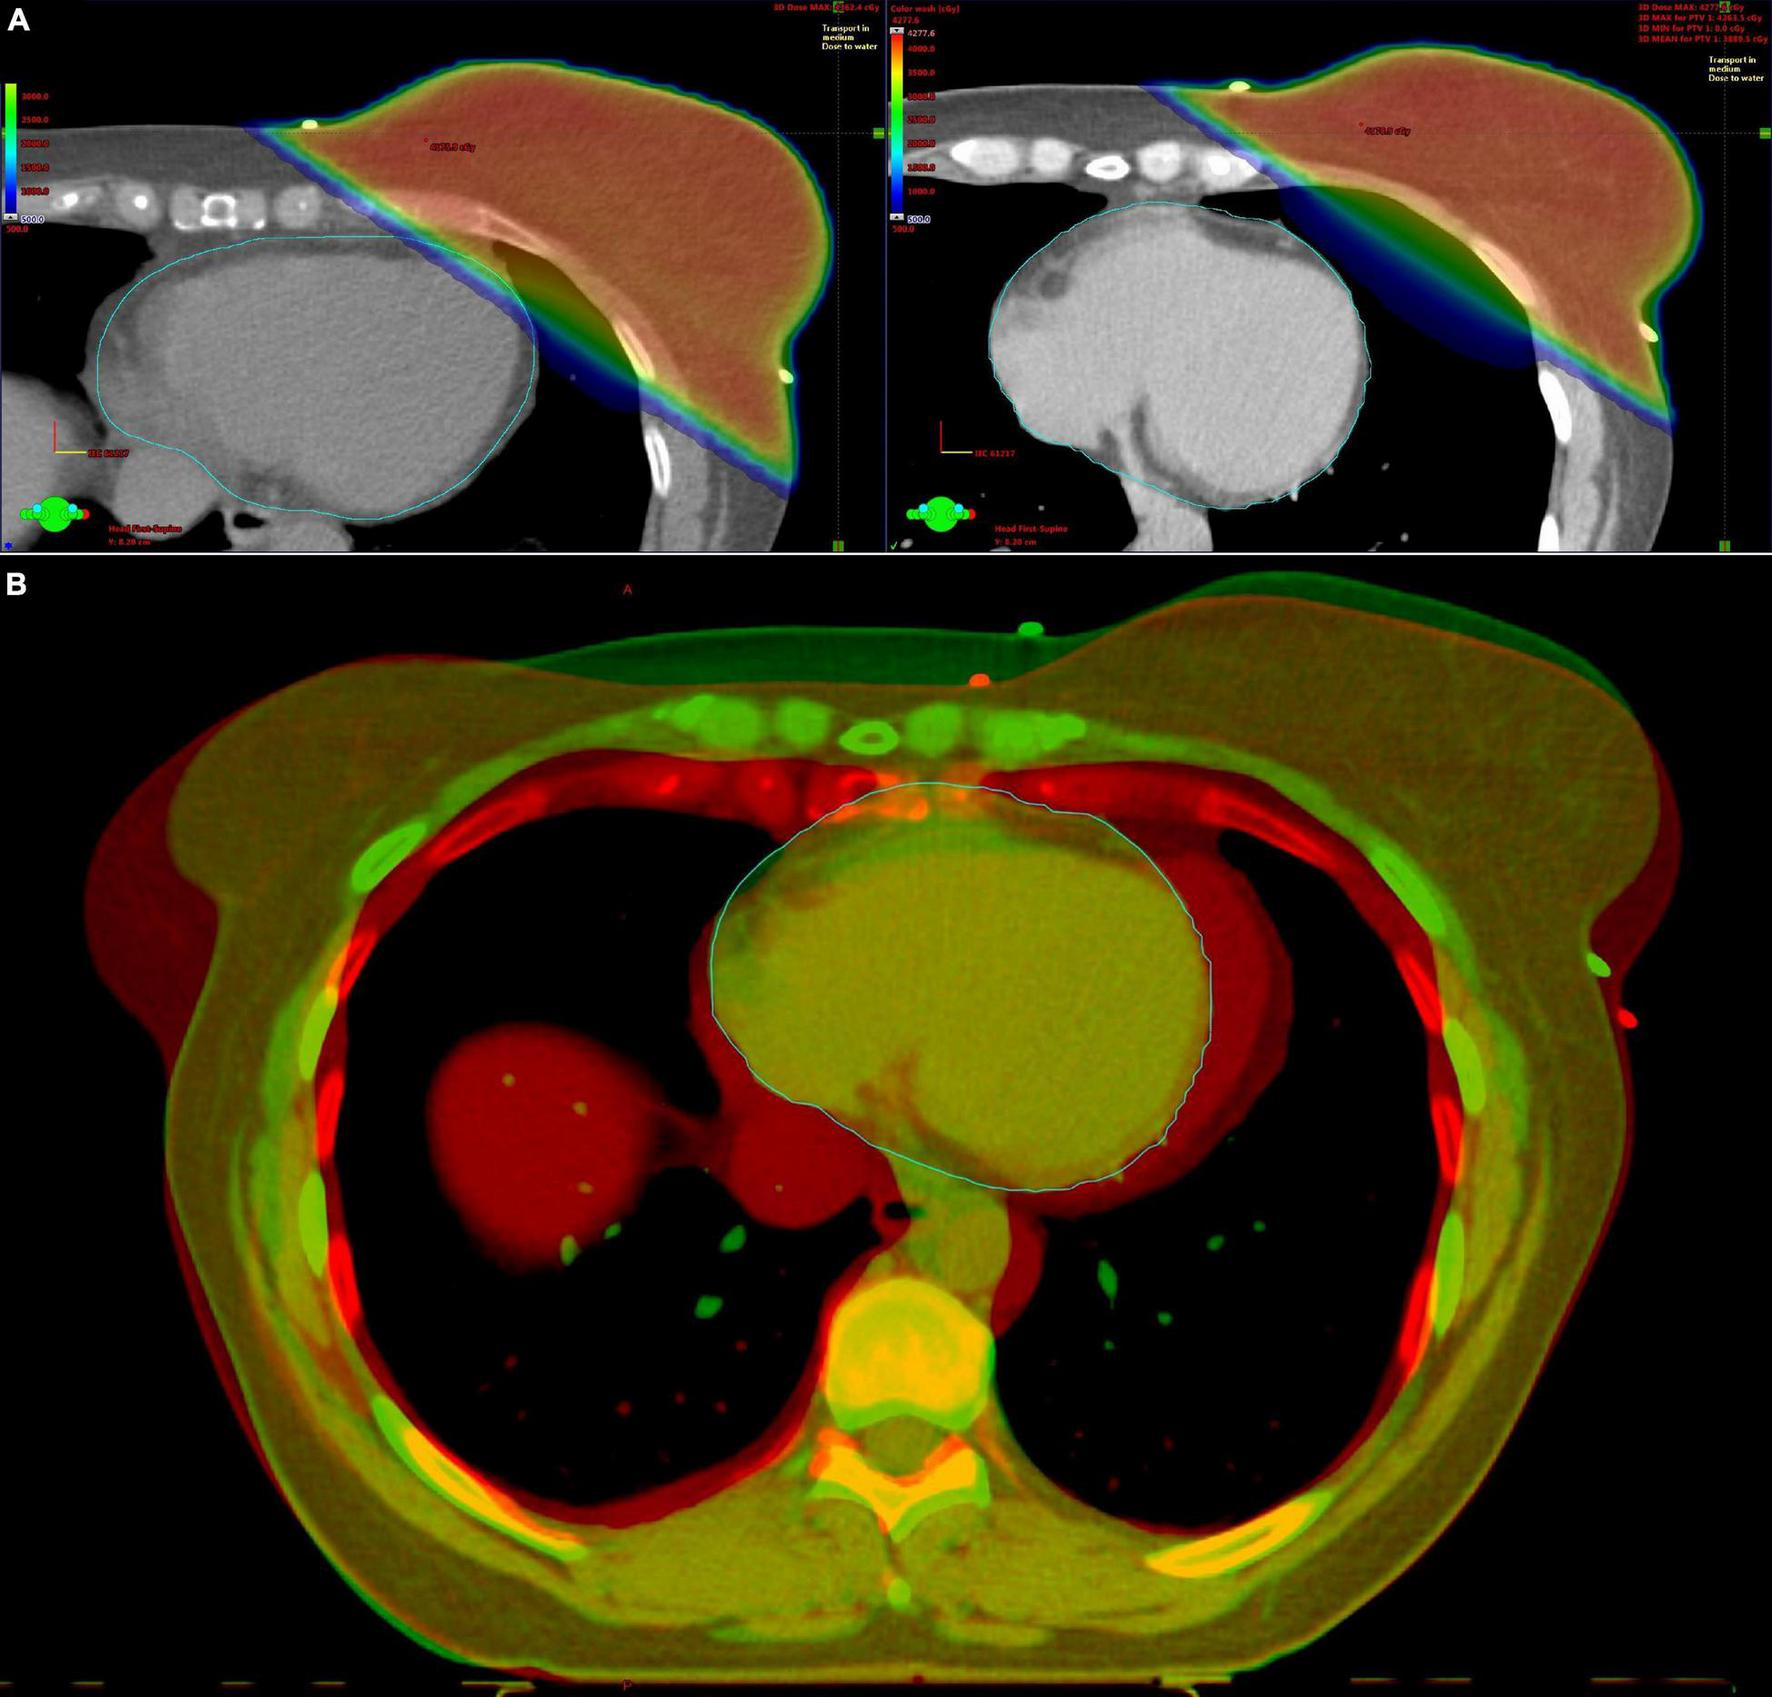

FIGURE 1

Deep inspiration breath hold (DIBH) radiotherapy for left-sided breast cancer. (A) Axial computed tomography slices with radiotherapy plan at the same level of the breast in free breathing (left) and DIBH (right). The distance between the heart and the breast is greater in DIBH, minimizing the radiation of the heart. (B) Fusion image of the free breathing (red color) and DIBH (green color) computed tomography scan.